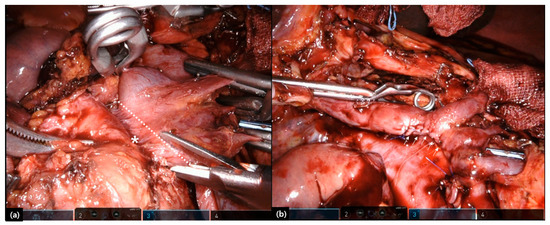

- Choi, M.; Lee, S.J.; Shin, D.M.; Hwang, H.K.; Lee, W.J.; Kang, C.M. Laparoscopic repeated pancreatectomy for isolated local recurrence in remnant pancreas following laparoscopic radical pancreatectomy for pancreatic ductal adenocarcinoma: Two cases report. Ann. Hepatobiliary Pancreat Surg. 2020. Forthcoming. [Google Scholar]